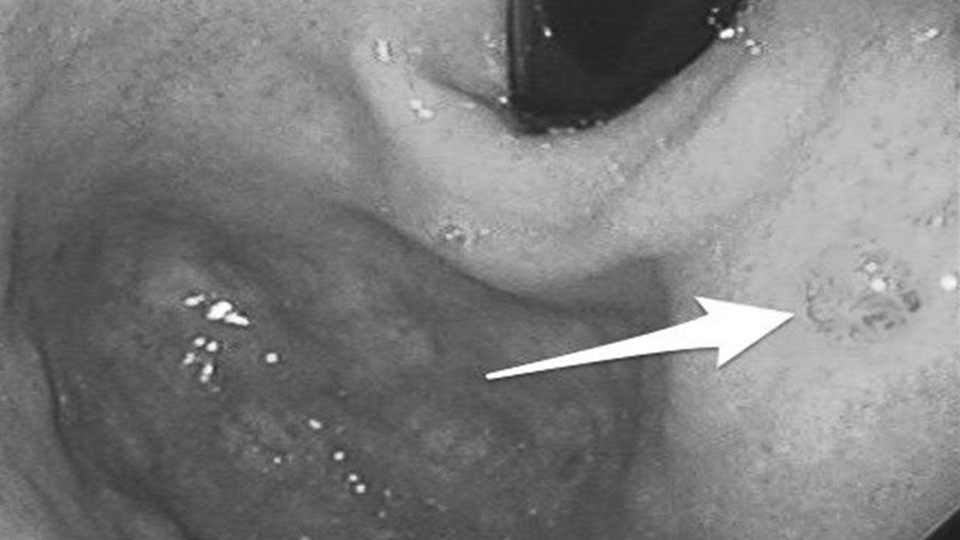

Thực tế, dạ dày không “bỗng nhiên hỏng”. Trước khi chuyển biến xấu, cơ quan này thường phát tín hiệu cảnh báo trong thời gian dài, nhưng vì triệu chứng mơ hồ, nhiều người dễ bỏ qua. Đáng lo hơn, không ít trường hợp chỉ phát hiện khi nội soi, lúc đó nguy cơ đã bước sang giai đoạn trung hoặc muộn.

Theo Cơ quan Nghiên cứu Ung thư Quốc tế (IARC), bệnh thường tiến triển qua một quá trình dài: viêm mạn tính, tổn thương niêm mạc, tăng sinh bất thường rồi mới chuyển thành ung thư.

Cơ chế này chịu tác động của nhiều yếu tố. Nhiễm vi khuẩn Helicobacter pylori (HP), ăn mặn kéo dài hoặc thói quen sinh hoạt thất thường đều có thể làm suy yếu lớp bảo vệ niêm mạc dạ dày. Khi quá trình tổn thương và sửa chữa lặp lại nhiều lần nhưng không hoàn chỉnh, niêm mạc có thể xuất hiện “chuyển sản ruột” - một dạng tổn thương tiền ung thư.

Các tổng quan trên tạp chí The Lancet Oncology cho thấy nếu can thiệp từ giai đoạn tiền ung thư, tiên lượng có thể cải thiện hơn 50%. Tuy nhiên, điểm khó là giai đoạn này hầu như không gây đau dữ dội, mà chỉ là những thay đổi nhẹ, dễ bị xem nhẹ.

Đối với người trên 40 tuổi hoặc có triệu chứng kéo dài, nội soi dạ dày định kỳ là phương pháp quan trọng giúp phát hiện sớm bất thường. Ngoài ra, chế độ dinh dưỡng đầy đủ protein, rau xanh cũng góp phần hỗ trợ phục hồi niêm mạc và ổn định chức năng tiêu hóa.